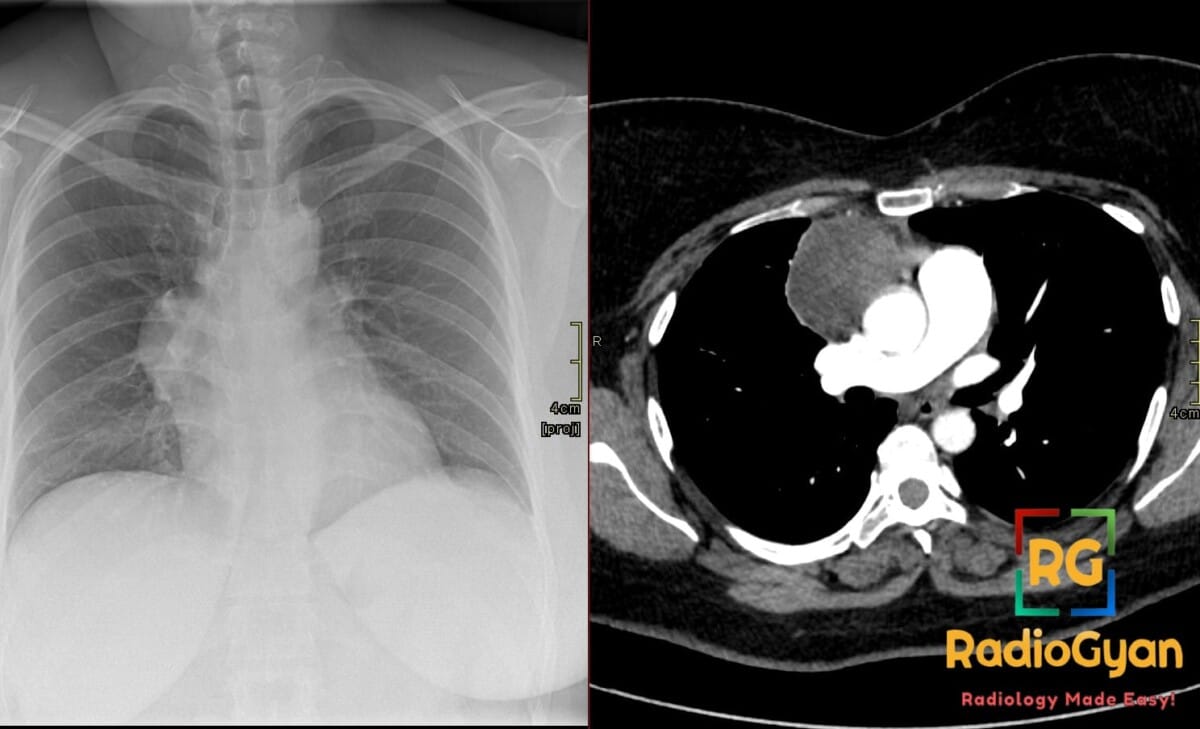

Supramesocolic spaces Axial View: CT image and corresponding illustration

Supramesocolic spaces Coronal View: CT image and corresponding illustration